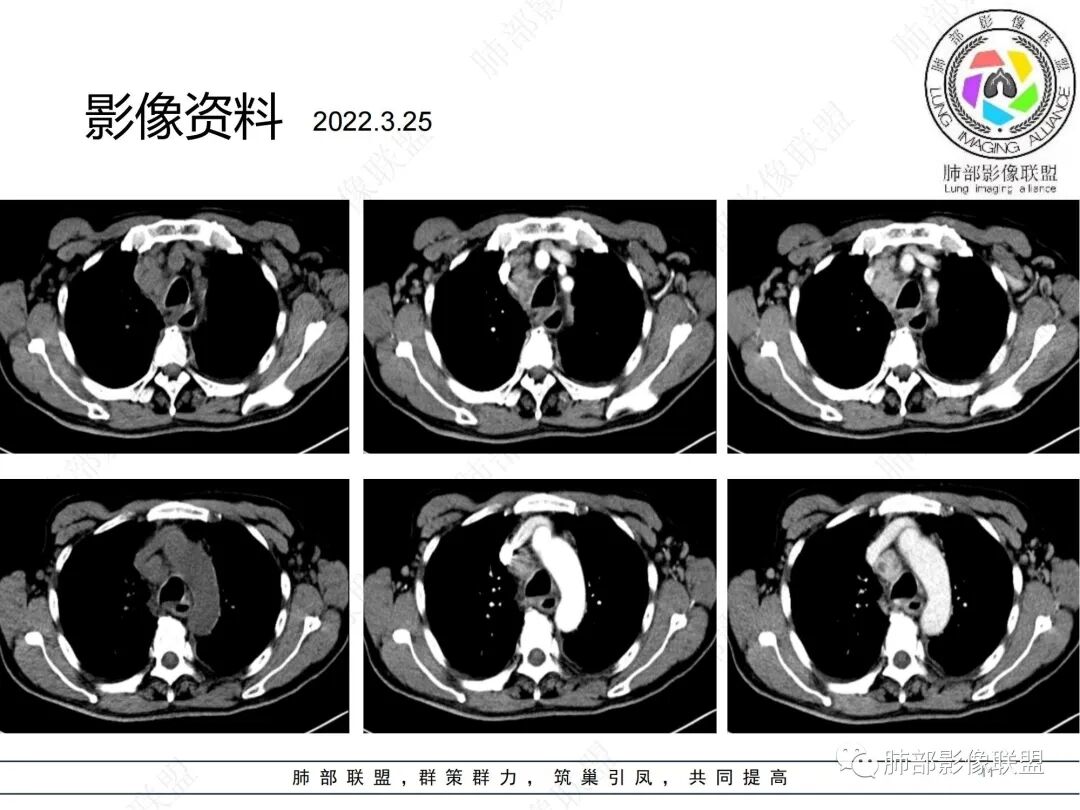

1、 临床特点:老年男性,慢性病程,午后低热为主,既往抗结核治疗有效,停药后复发,MTB抗原ESAT-6和CFP-10阳性,T-SPOT实验(+);查体:右颈部及右腹股沟区多发肿大淋巴结。

2、影像特点:双肺多发结节及条索影,边缘清晰,右肺上叶可见网格影,右侧胸腔少量积液;颈部、纵膈及腹部多发淋巴结肿大,大部淋巴结强化不均,呈环形强化,内部见低密度坏死区,部分淋巴结坏死不明显,尤其是腹部淋巴结密度较均匀。

3、综上:病人低热不具有特异性,结核及淋巴瘤都可以存在。胸部影像、治疗经过及实验室检查更支持结核,但是全身广泛淋巴结肿大,在继发性肺结核中并不常见,EB病毒核酸阳性,虽然不具有特异性,还是应该警惕淋巴瘤。

最终病理结果证实;淋巴结结核和T淋巴母细胞淋巴瘤(非霍奇金淋巴瘤)并存。